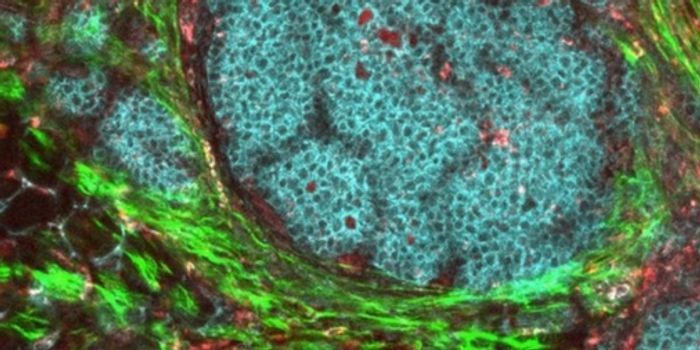

JUN 29, 2017CancerMost cancers kill by invading distant parts of the body where treatment is more difficult to reach. But cancer’s a ...

OCT 19, 2017CancerTo fuel their growth and edge out healthy cells, breast cancer cells recycle a waste product into nutrients, researchers ...